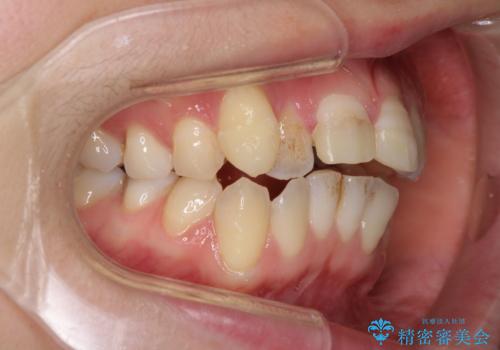

転んで前歯が欠けた 折れた前歯をきっかけに矯正治療で歯列をきれいに整える

- 転倒により前歯の一部が欠けてしまったとのことで来院された患者様です。

神経が保存できる歯、神経を除去しなければならない歯、抜歯が必要な歯があり、ブリッジやインプラントなどによる治療を提案しました。

元々歯並びが気になっていたとのことで、前歯の治療を行うことを契機に矯正治療も行うこととしました。

本来であれば積極的に小臼歯を抜歯して口元を下げても良いのですが、前歯を1本抜歯しないといけなくなったため、非抜歯矯正をインビザラインを用いて行うこととしました。